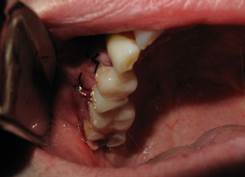

| Extracción del resto radicular y eliminación de la infección en periapice del premolar adyacente | |